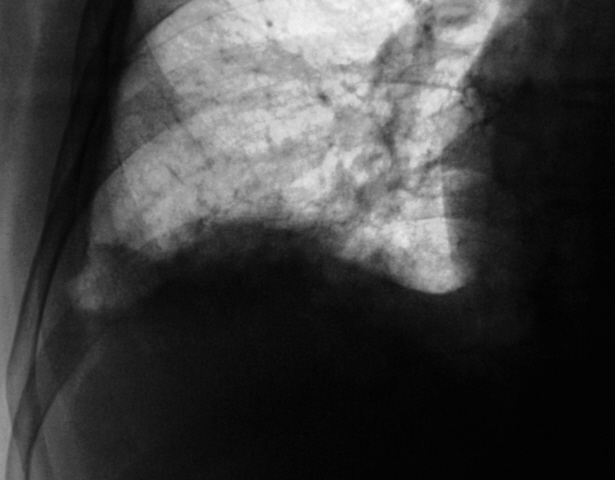

Сегодня произвели "очередной контроль". Произвели рентгенографию в прямой и правой боковой проекциях. Решили также произвести томографию в правой боковой проекции.

Катенёву В.Л.: На боковых томограммах, впечатление о инфильтрации с распадом в S10; томограммы, вероятно выполнены в положении лёжа, следовательо следует ожидать, что выпот растекся по грудной стенке и  не виден. С учётом характера распада, не исключаеиться туберкулёзный процесс.

О "выпоте" думали даже сначала, но только об осумкованном. Сегодня при дообследовании, "полостное образование" было неожиданной находкой, но о "туберкулёзной" этиологии, именно полостного образования, не думали. Но интересно, что пациент себя (с его слов) чувствует себя хорошо. ПО ВСЕЙ ВИДИМОСТИ, ОТПРАВИМ В ОБЛАСТЬ К ПУЛЬМОНОЛОГАМ.